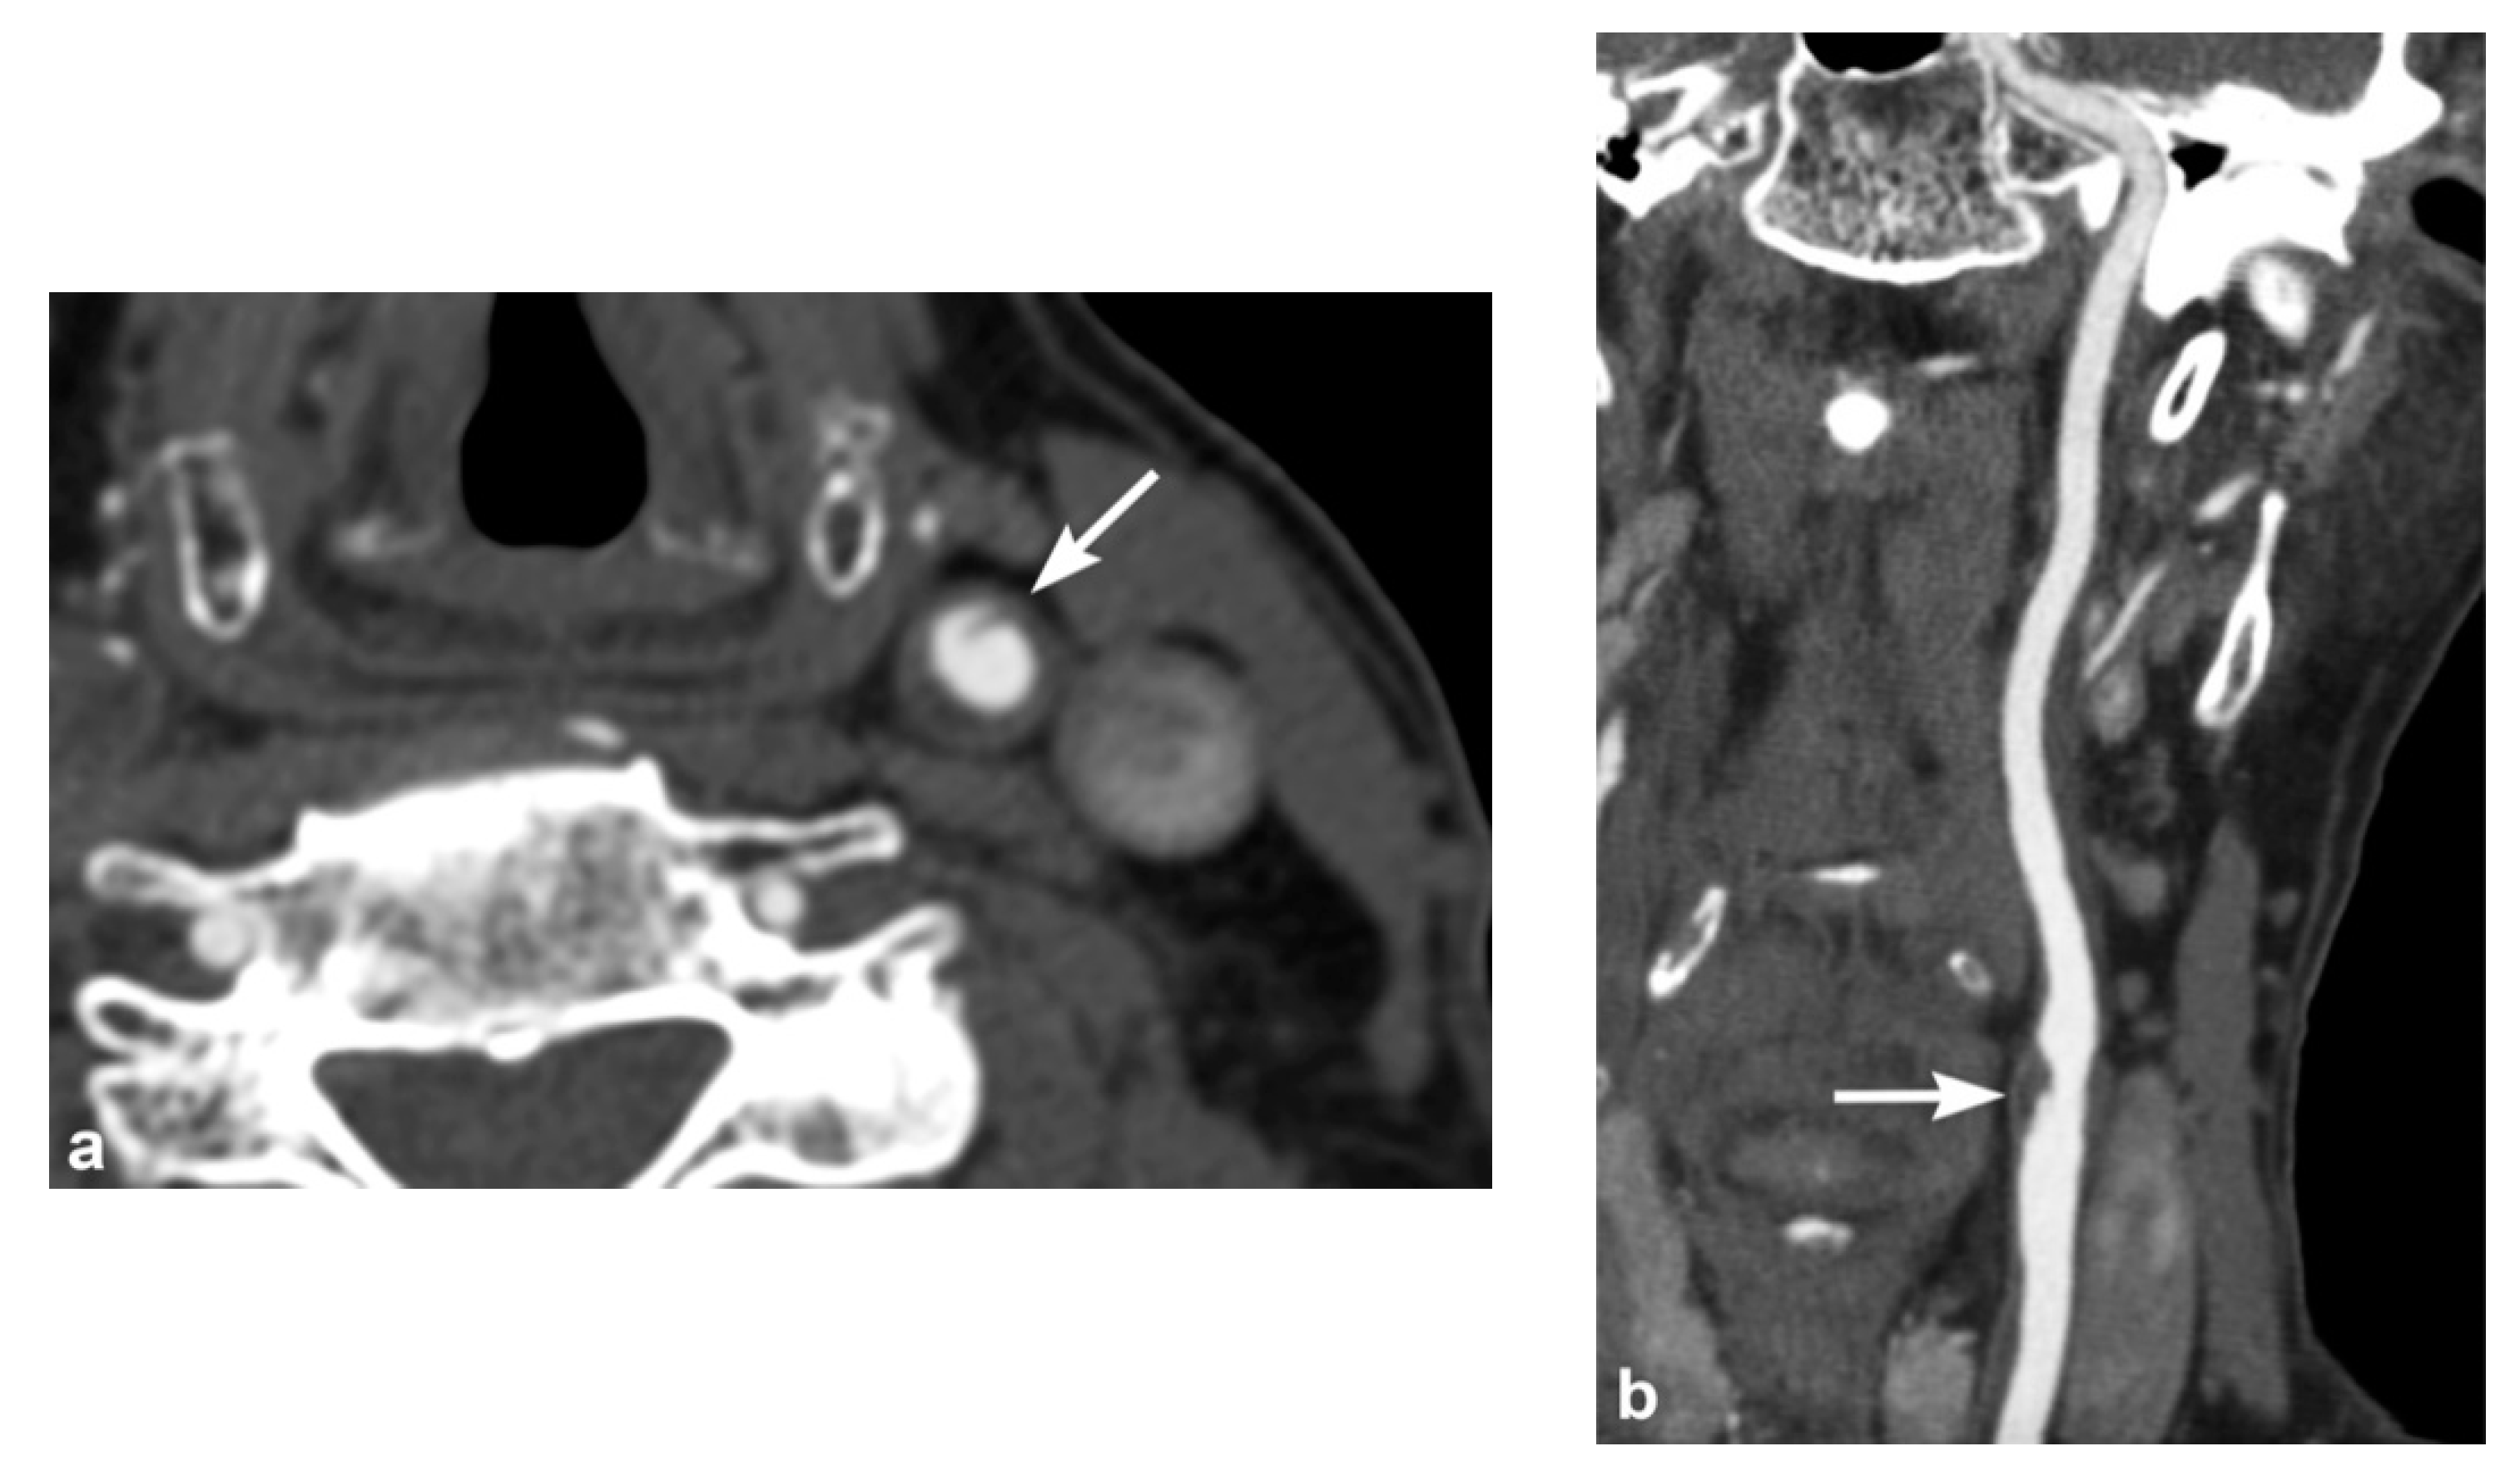

3. Imaging Findings of Arterial Injury